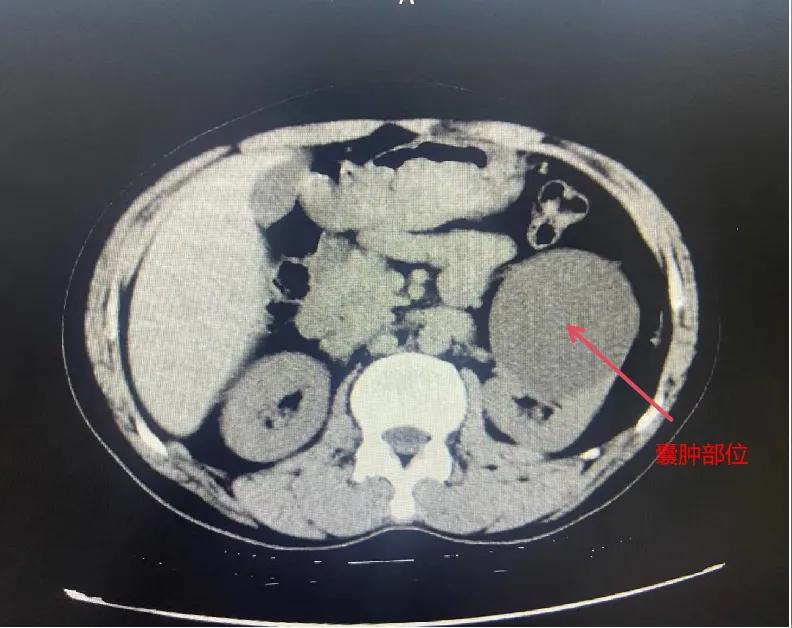

漯河市骨科醫(yī)院泌尿外科開展后腹腔鏡下腎囊腫去頂減壓術(shù)

近日,漯河市骨科醫(yī)院(漯河醫(yī)專二附院、漯河市立醫(yī)院)連續(xù)收治2例腎囊腫患者。泌尿外科主任閆衛(wèi)甫和副主任醫(yī)師王金柱等醫(yī)師團隊經(jīng)討論研究后,決定為患者采取后腹腔鏡下腎囊腫去頂減壓術(shù),經(jīng)過手術(shù)室、麻醉科等科室大力配合成功完成手術(shù)。

閆衛(wèi)甫表示,后腹腔鏡技術(shù)是一種微創(chuàng)外科手術(shù)方法,它通過在后腹腔(即腹膜后的空間)建立一個手術(shù)空間,利用腹腔鏡器械進行手術(shù)操作。這種技術(shù)特別適用于泌尿系統(tǒng)等后腹腔臟器的手術(shù)。與傳統(tǒng)手術(shù)相比具有創(chuàng)傷小、恢復快、并發(fā)癥少、視野清晰等優(yōu)點。與前腹腔鏡相比則具有對腹腔臟器干擾較少的優(yōu)點。目前,后腹腔鏡手術(shù)主要用于腎囊腫去頂減壓術(shù)、腎上腺腫瘤切除、早期腎癌根治術(shù)、腎腫瘤剜除術(shù)等。

腎囊腫是一種常見的腎臟良性疾病,其發(fā)病率逐年增加。近年來隨著腹腔鏡技術(shù)的迅速發(fā)展,后腹腔鏡下腎囊腫去頂減壓術(shù)成為治療腎囊腫的主要方法。該手術(shù)具有創(chuàng)傷小,手術(shù)時間短,術(shù)中出血少,術(shù)后康復快,出院時間短等優(yōu)點,并且術(shù)后復發(fā)率低,被認為是治療腎囊腫的理想術(shù)式。(盧 闖 聶方方 劉 旭 袁錦鈺)